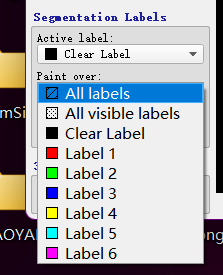

1.3.1 个性化标注

Active Label为激活的标签,表示当前使用的标柱类型,此时选择label 1为红色,说明使用红色进行标注paint Over为允许标注的范围,All labels允许对所有的标签进行标注,包括覆盖之前的标注;All visiable label是对所有可见的标签进行标注,如图,红色所在的位置则不能标注,

paint over续:使用Active Label=Label1; paint Over=Clear Label标注时,只允许对没有标注的区域标注,如图,同样的,如果paint over=Label1(red), active label = label3则蓝色只能在红色上标注